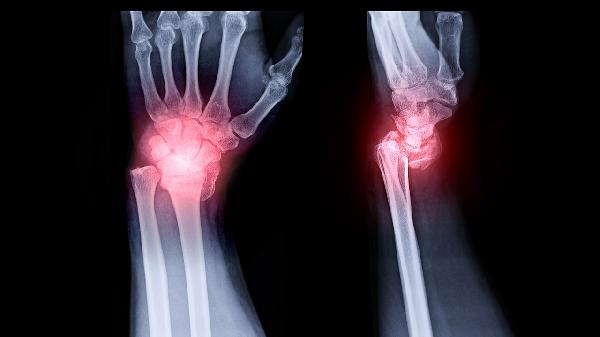

当骨折存在明显移位、关节面受累或合并神经血管损伤时,可能导致拇指对掌功能受限或创伤性关节炎。此类情况需通过手术复位内治疗,若遗留关节活动度丧失超过15%或握力下降超过25%,则可能被评定为轻伤二级。开放性骨折或合并肌腱损伤者,其损伤程度需根据愈后功能恢复情况重新评估。

建议患者及时至骨科就诊,完善X线或CT检查明确骨折情况。治疗期间应保持患肢抬高,避免早期负重活动,定期复查观察骨折愈合进度。康复期可在医生指导下进行拇指屈伸及对掌功能训练,饮食注意补充钙质和优质蛋白,如牛奶、鱼肉等促进骨痂形成。